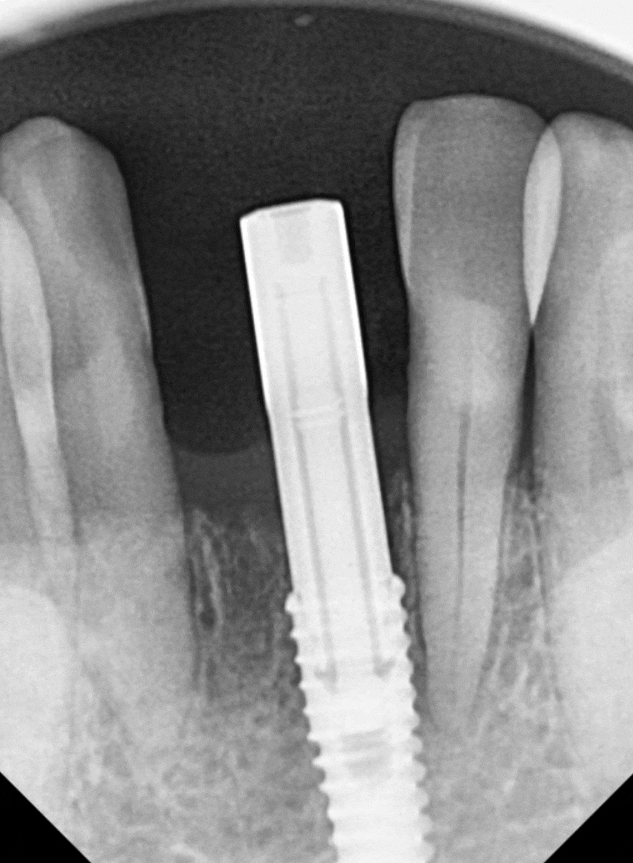

치석으로 인해 뼈가 많이

약해진 상태였기에,

발치 당일 뼈이식과

임플란트 식립을 함께 진행했습니다.

식립 3개월 뒤,

뼈와 임플란트가 단단히 굳은 것을 확인하고

디지털 구강스캐너로 본을 떴습니다.

뿌리는 1개지만,

보철물은 2개가 들어갔습니다.

전혀 어색하지 않고

주변 치아와 자연스럽게 어우러지죠?

옆 치아의 길이와도 대칭을 이루어

심미적으로도 아주 만족스럽게 마무리되었습니다.